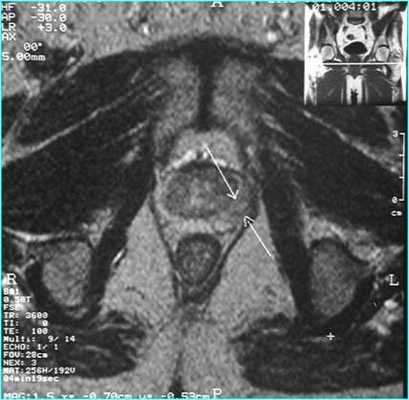

Пациент С., 1945 года рождения, считает себя больным с 2012 г., когда впервые отметил затруднения при мочеиспускании, однако к врачам не обращался. В июле 2016 г. при плановом обследовании по месту жительства выявлено повышение ПСА до 276 нг/мл, выполнена трансректальная биопсия предстательной железы под ультразвуковым контролем. Больной для дальнейшего обследования и лечения обратился в поликлинику МНИОИ им. П.А. Герцена. При гистологическом исследовании, пересмотре стекол и блоков гистологических препаратов в МНИОИ им. П.А. Герцена выявлен инфильтративный рост ацинарной аденокарциномы 7 (4+3) баллов по Глисону, занимающей до 80% площади биоптатов. Пациент самостоятельно выполнил ПЭТ/КТ с холином. По данным ПЭТ/КТ, в обеих долях простаты определяются очаги накопления радиофармпрепарата (РФП) неоднородного характера, с наиболее выраженным накоплением РФП до макс. SUV 12,09 в периферической зоне слева и переходных зонах предстательной железы с обеих сторон (рис. 1), Рис. 1. Компьютерная томограмма малого таза (а). Накопление РФП в предстательной железе (б). в семенных пузырьках слева и справа, а также в наружном подвздошном лимфатическом узле слева макс. SUV 4,47, размером 1,3×0,7 см.

Пациент К., 1965 года рождения, при плановом обследовании в поликлинике по месту жительства в марте 2017 г. выявлено повышение уровня ПСА до 6,5 нг/мл, в связи с чем в ГКБ № 29 Москвы выполнена трансректальная биопсия предстательной железы, гистологически верифицирована ацинарная аденокарцинома 6 (3+3) баллов по Глисону. Больной самостоятельно обратился в МНИОИ им. П.А. Герцена. При пересмотре стекол препаратов биопсии предстательной железы в условиях патоморфологического отделения МНИОИ им. П.А. Герцена на фоне гиперплазии предстательной железы с очагами атрофии в 5 фрагментах из 12 выявлен рост ацинарной аденокарциномы 7 (4+3) баллов по Глисону, занимающей до 100% площади столбиков. По данным УЗИ и МРТ малого таза, предстательная железа размером 42×34×30 мм, объемом до 30 см 3 (рис. 3). Рис. 3. Магнитно-резонансная томограмма малого таза.